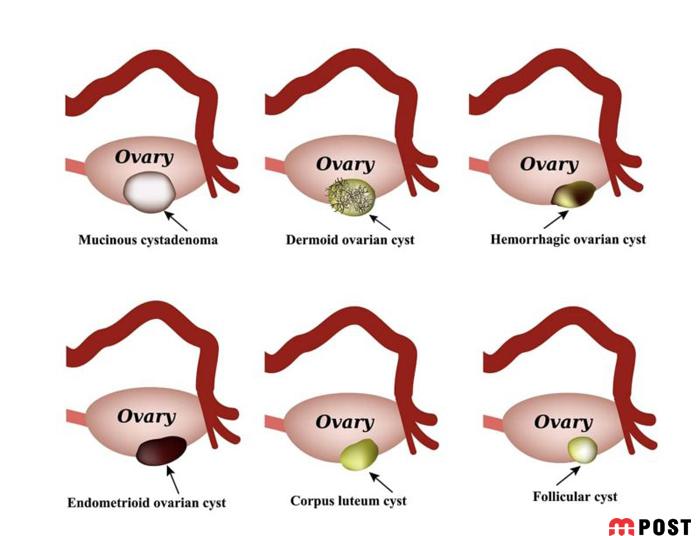

قبل از توضیح در مورد کیست هموراژیک تخمدان؟ لازم است بدانید که کیست تخمدان بیماری زنانهای است که از تشکیل یک یا چندین کیست غیرطبیعی در تخمدان سرچشمه میگیرد. کیستهای تخمدان ساکهایی حاوی مایع هستند که درون تخمدان یا روی آن رشد می کنند.

انواع مختلفی از کیستهای تخمدان وجود دارد که شایعترین آن کیست های فولیکولی است. این کیست ها در یکی از فولیکولهای تولیدکننده تخمک ایجاد میشود.

کیست های ساده (فولیکولی) با رشد قسمتی از تخمدان و تجمع مایع داخل آن مشخص میشوند، اندازه آنها معمولاً بالای ۳ سانتیمتر است و نباید با فولیکول تخمک که در زمان تخمکگذاری گاهی حتی به اندازه ۲۵ میلیمتر میرسد، اشتباه شوند.

نوع دیگری از کیست های تخمدان هستند که کسیت هموراژیک یا خونریزی دهنده نامیده می شوند. البته، این کیست ها بر خلاف اسمشان، معمولاً تأثیری بر باروری ندارند.

کیست های تخمدان کیسه ها یا کیسه های پر از مایع در داخل یا روی سطح تخمدان هستند. کیست های تخمدان خونریزی دهنده در طول تخمک گذاری زمانی که تخمک از طریق فولیکول تخمدان روی سطح آن آزاد می شود، ایجاد شده و آن فولیکول به داخل کیست خونریزی می کند. پزشکان نمی دانند چرا این اتفاق می افتد.